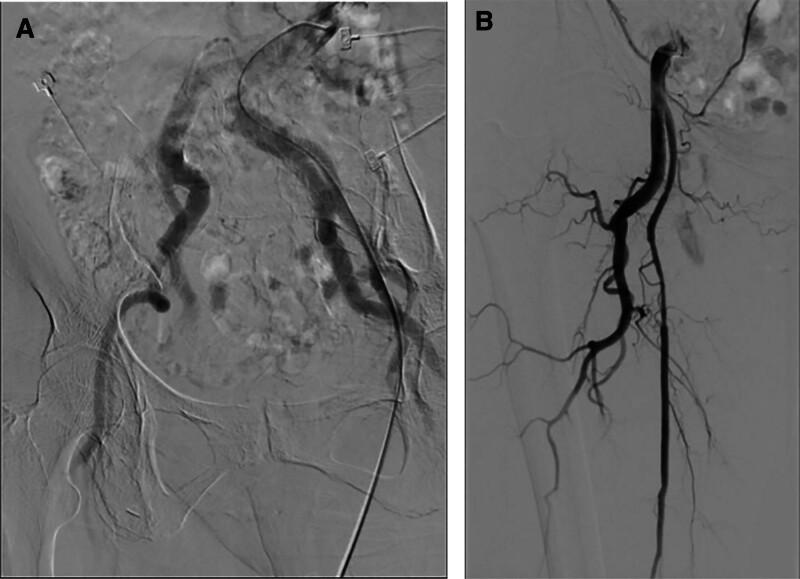

A case report of bilateral persistent sciatic artery: Bilateral aneurysm with thromboembolism of the right lower extremity.

Acute thromboembolism in the right leg, bilateral PSA, and bilateral aneurysm.

After the super-selective embolization, lower limb arterial thrombolysis treatment was performed. After symptom relief, a computed tomography angiography was conducted to clarify the vascular variations.

在超选择性栓塞后,进行下肢动脉溶栓治疗。症状缓解后,行 CT 血管造影以明确血管变异情况。